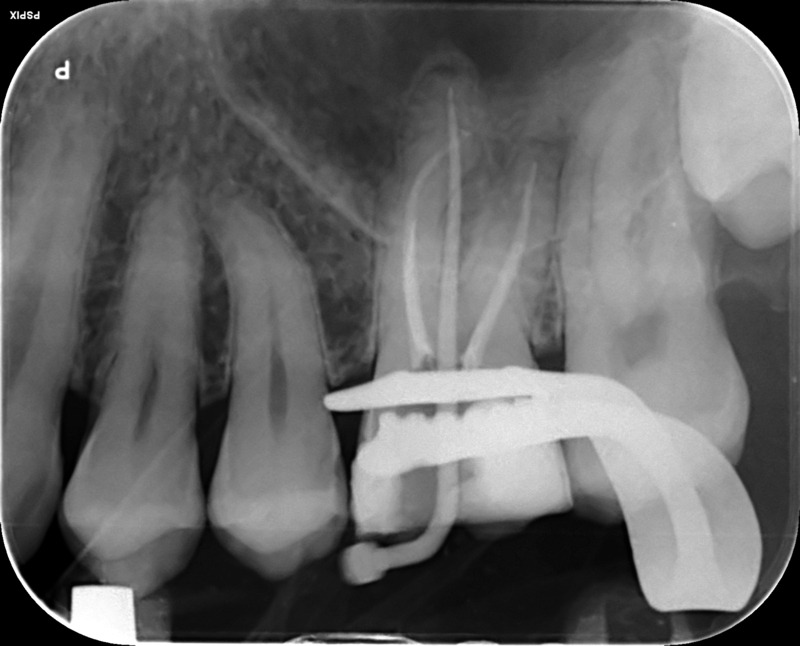

UL6 Internal inflammatory resorption perforating palatal root. Repaired with MTA.

12 month review (crown carried out by GDP)